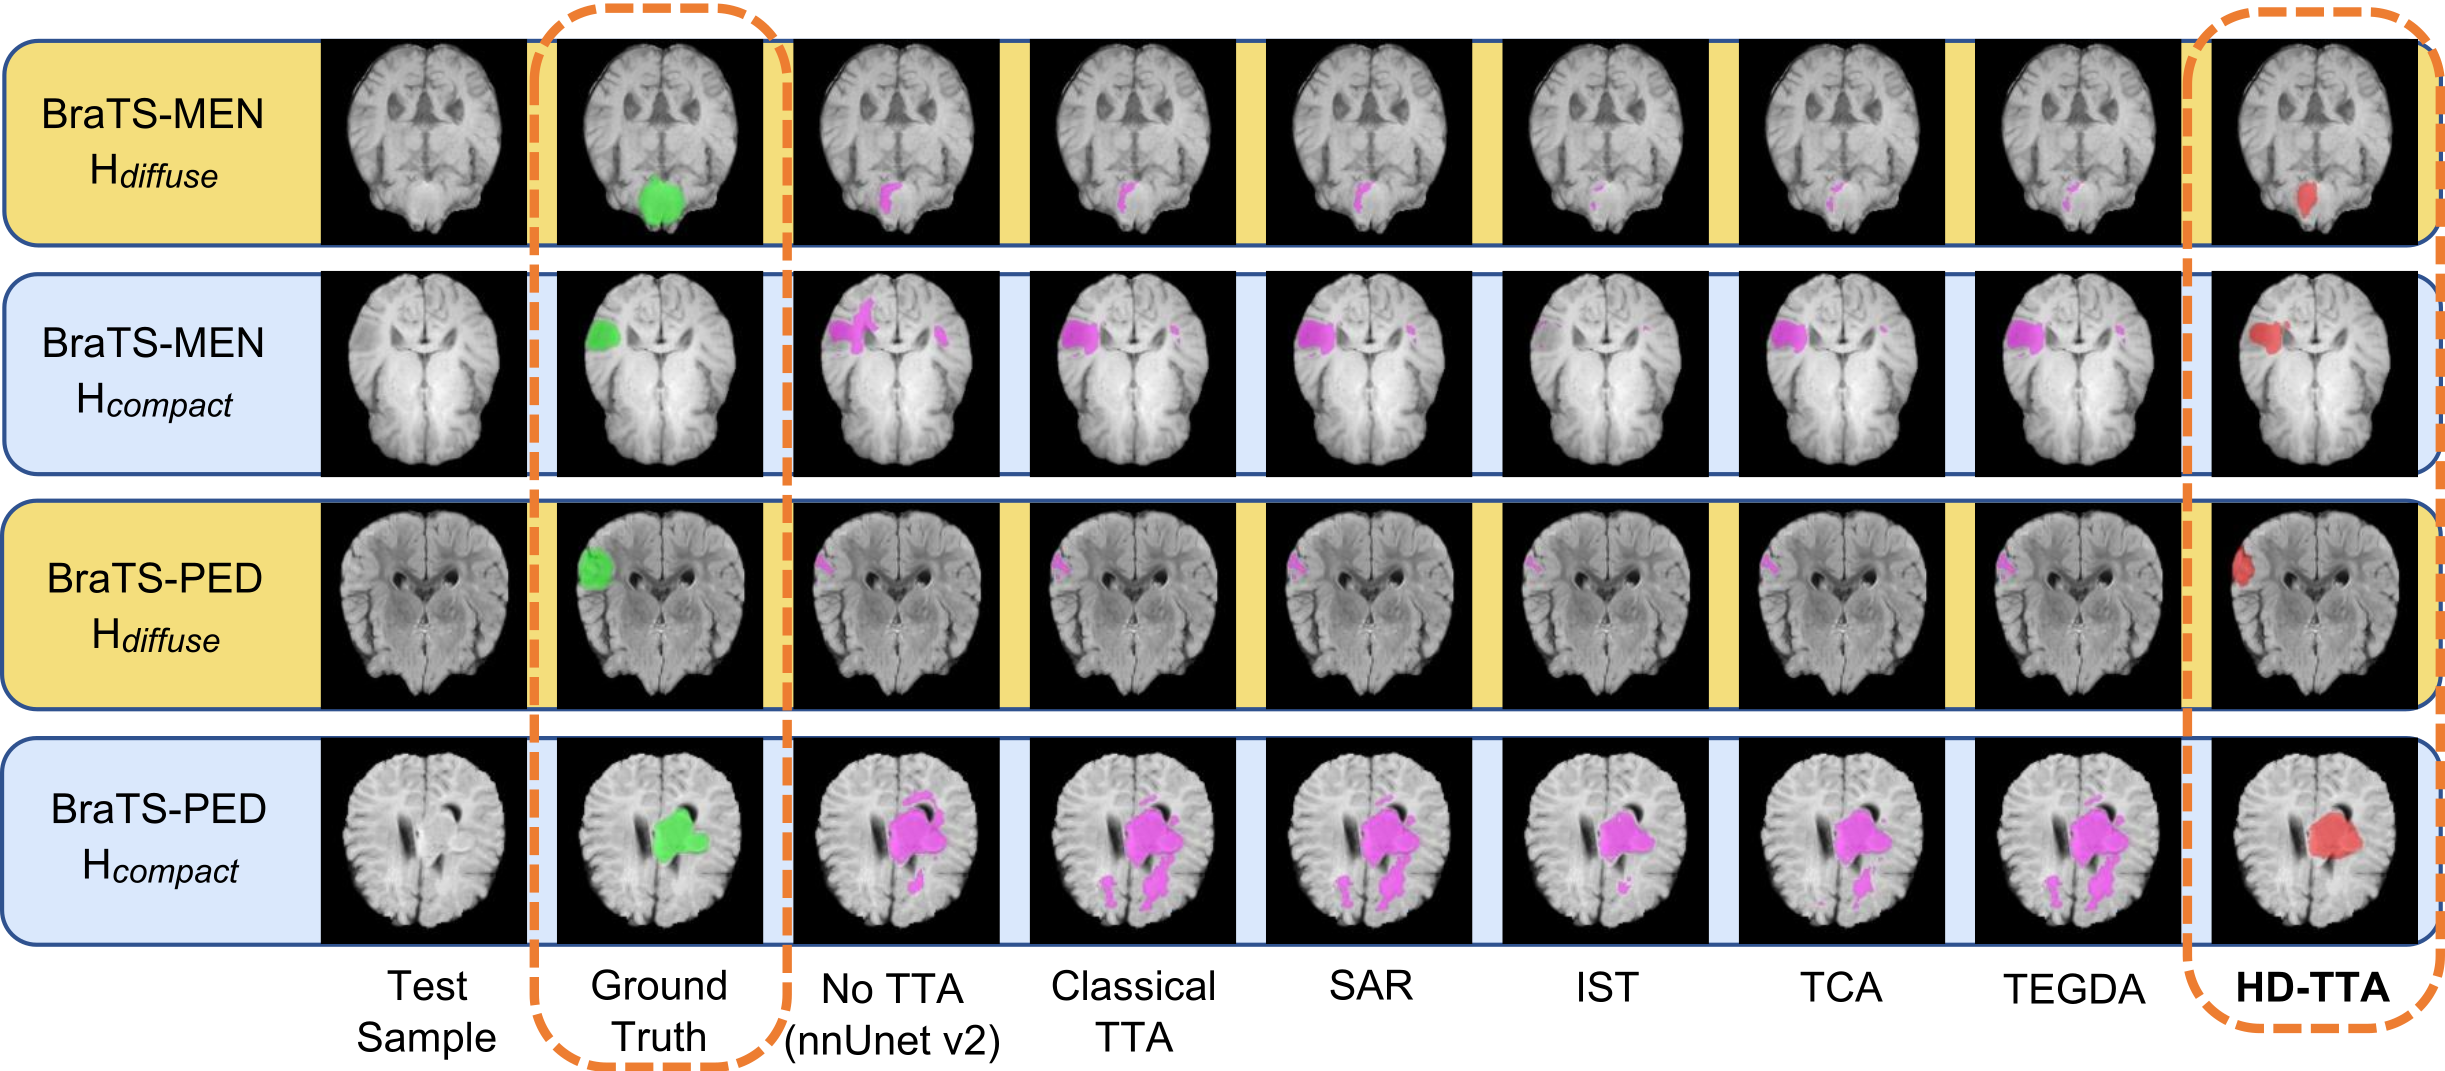

Qualitative Mechanisms and Visual Analysis. Fig. 3 provides qualitative evidence for why the safety gains occur. Adaptation on representative BraTS-MEN cases (Fig. 3, Rows 1-2): The backbone nnU-Net v2 prediction (marked as No TTA) misses significant portions of the tumor (in magenta color). Entropy-based methods (SAR, TCA) fail to recover this missed tissue because they lack a mechanism to initiate growth in low-confidence regions. In Row 1, HD-TTA successfully selects HdiffuseH_{\text{diffuse}}, leveraging the inflation objective to relatively recover the missed tumor volume (red). Conversely, in Row 2, HD-TTA correctly selects HcompactH_{\text{compact}} to denoise the primary nnU-Net prediction and cleanly eliminate the spurious false-positive island; notably, even the strongest baseline, TCA, fails to fully suppress this artifact. Adaptation on representative BraTS-PED cases (Fig. 3, Rows 3-4): In Row 3, the backbone nnU-Net v2 under-segments the tumor, prompting HD-TTA to correctly select HdiffuseH_{\text{diffuse}} to recover the missing boundary, when other baselines fail to recover to a similar extent. Conversely, in Row 4, the backbone nnU-Net v2 produces a severe over-segmentation with a prominent spurious noise island. Blind adaptation methods either preserve or exacerbate these high-confidence artifacts (as seen with Classical TTA). HD-TTA’s Gatekeeper flags the instability and selects HcompactH_{\text{compact}}, utilizing gravity and smoothness constraints to cleanly eliminate the false positives and restore a plausible tumor shape. Notably, while IST attempts to suppress this artifact, it fails to remove it entirely.

Refer to caption

Figure 3: Qualitative comparison on representative BraTS-MEN (Rows 1-2) and BraTS-PED cases (Rows 3-4).